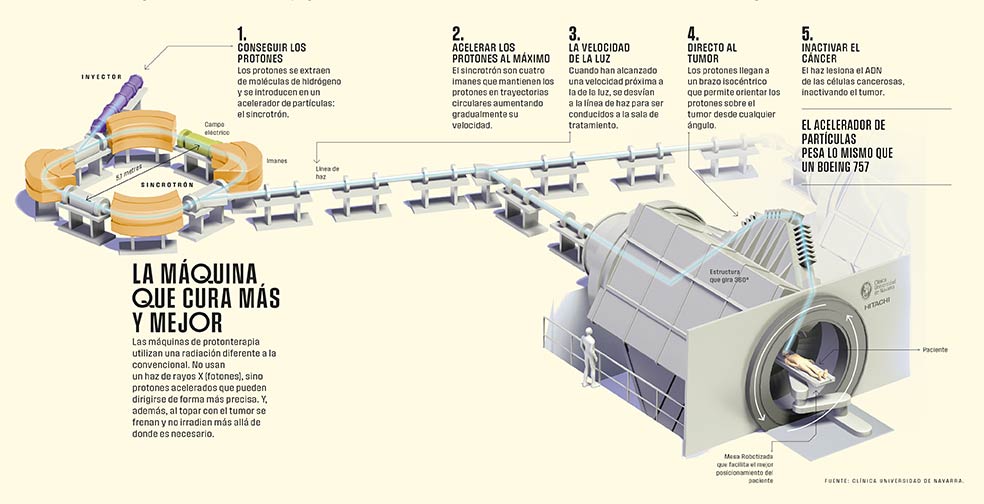

¿Cómo funciona?

Menor toxicidad y mayor precisión. La terapia con protones permite aumentar la dosis de radiación que se aplica al tumor al tiempo que minimiza dispersiones innecesarias. Y todo ello porque se trata de una radiación diferente a la convencional. Mientras la habitual se basa en un haz de rayos X (fotones), la protonterapia utiliza partículas aceleradas (protones) que pueden dirigirse de forma más precisa. ¿La razón? Las características físicas de los protones, que, por su masa, no sufren alteraciones en su trayectoria. De este modo consiguen depositar la mayor parte de su energía dentro del tumor y, además, al topar con este se frenan inmediatamente y no irradian más allá. La doctora Carmen Ares lo explica con un símil: «Imaginemos la trayectoria de esos haces como si fuera una autopista. En la radioterapia tradicional llegan a la zona que se quiere radiar, pero van depositando ciertas dosis en los tejidos que atraviesan y, además, siempre hay otra dosis de salida». Por eso, la protonterapia está especialmente indicada en tumores que requieren dosis muy altas y que están localizados cerca de zonas u órganos muy sensibles a la radiación y en tumores pediátricos, «ya que los órganos están todavía en desarrollo y es aún más importante evitar irradiarlos», continúa.